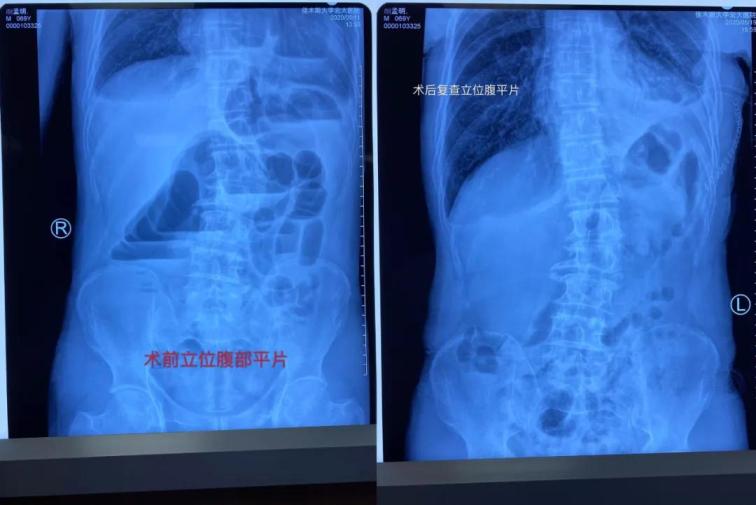

患者顏某某,男,69歲,因“間斷性腹痛腹脹、惡心嘔吐肛門停止排氣排便4天”于5月11日17時22分經(jīng)門診掛號診療,以“腸梗阻”收住我院普外一科。主管醫(yī)生張志光詳細(xì)詢問患者病史、全面查體,結(jié)合相關(guān)輔助檢查,入院給予禁食水、胃腸減壓和補液治療。

雖然患者表現(xiàn)為腸梗阻癥狀,但是從事普外多年、細(xì)心的張醫(yī)生對患者的胸部CT心前區(qū)顯示低密度影像產(chǎn)生疑問,懷疑膈疝可能,并于5月12日晨找胸外科周鋼主任會診。 周鋼主任結(jié)合病史、癥狀、查體、輔助檢查,高度懷疑膈疝中的心膈角疝,疝內(nèi)容物考慮結(jié)腸可能,因患者目前表現(xiàn)為腸梗阻,腸管卡壓時間長易導(dǎo)致壞死,且胸部CT表現(xiàn)心包填塞,此時動脈血壓已經(jīng)下降,靜脈血壓升高,脈壓差縮小,已經(jīng)出現(xiàn)休克。

術(shù)中發(fā)現(xiàn)橫結(jié)腸疝入心包并嵌頓,腸管高度擴張,已經(jīng)顏色較暗,同時疝入心包腔內(nèi)還有大網(wǎng)膜,已表現(xiàn)血運障礙。心臟嚴(yán)重受壓,近乎停止跳動。緊急切開擴大疝環(huán),觀察疝入的腸管和大網(wǎng)膜血運情況,約觀察30分鐘血運障礙恢復(fù)后,小心將疝入的腸管和大網(wǎng)膜還納入腹腔。心包腔恢復(fù)原有空間,心臟開始恢復(fù)節(jié)律性跳動。術(shù)后病人轉(zhuǎn)入胸外科病房,監(jiān)護(hù)綜合治療護(hù)理,目前患者恢復(fù)良好。